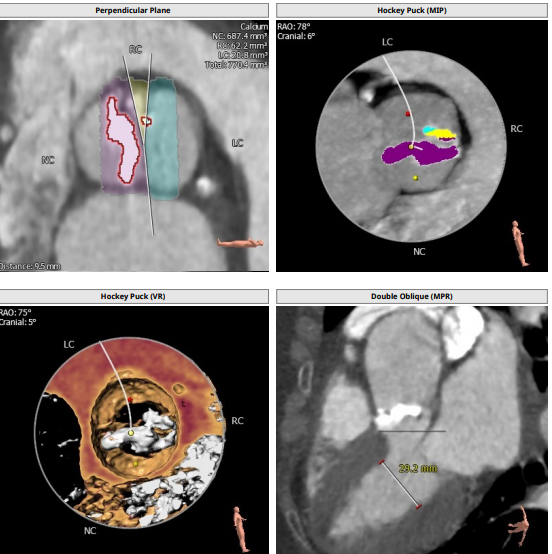

此例患者大横位Type0型二叶瓣,瓣环径23.1,LVOT22.6,Stj35.9,左冠高度11.8,右冠19.5,术前根据总体结构使用20MM球囊预扩,抓捕器辅助瓣膜通过横位结构跨瓣,术前预装VenusA23号瓣膜。

根部解剖:

发生瓣叶切割,无窦侧瓣叶切割,Type0结构形变为类三叶瓣结构。